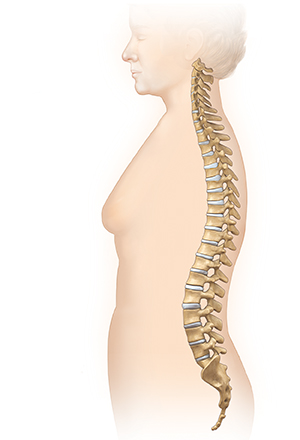

A normal spine, when viewed from behind, appears straight. However, a spine affected by kyphosis has a forward curvature of the back bones (vertebrae) in the upper back area, giving an abnormally rounded or humpback appearance. This is sometimes known as roundback or a dowager's hump.

Kyphosis is a curvature of the spine measuring 50 degrees or greater on an X-ray. The normal spine can bend from 20 to 45 degrees of curvature in the upper back area. Kyphosis is a type of spinal deformity.

| Normal spine. |

| Spine with kyphosis. |